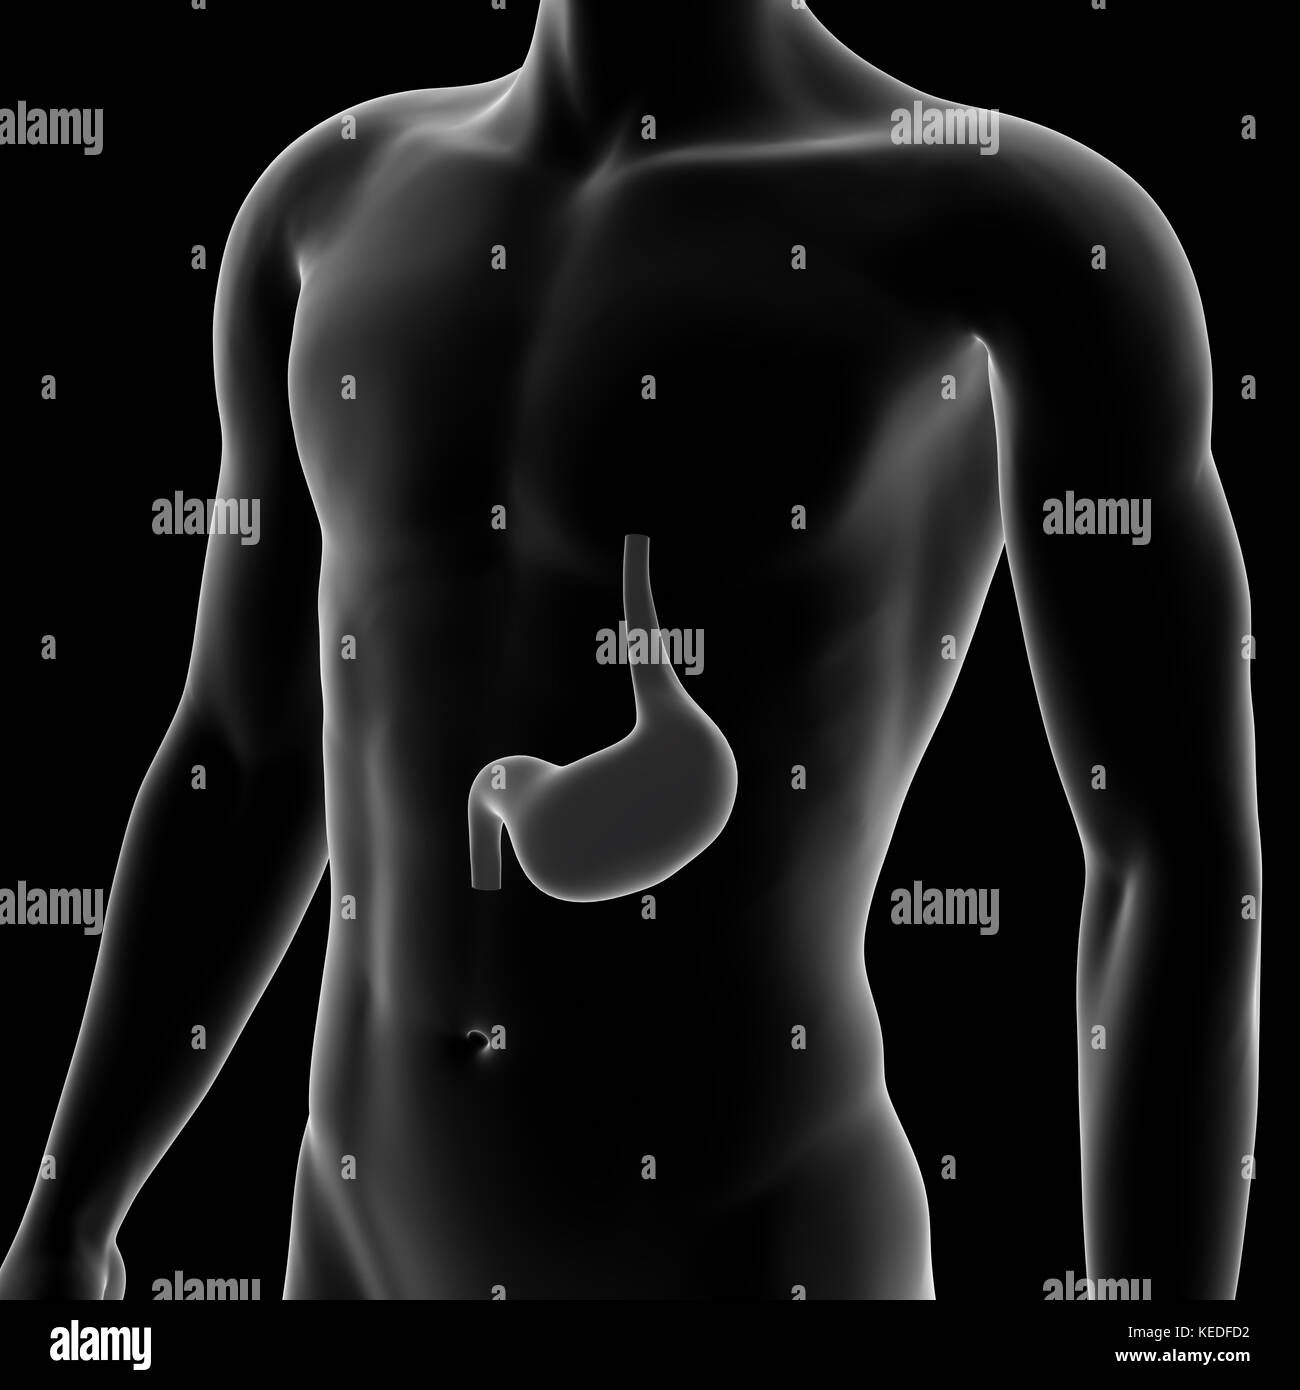

Stomach, Internal Organ, Human Body Stock Photohttps://www.alamy.com/image-license-details/?v=1https://www.alamy.com/stock-image-stomach-internal-organ-human-body-163795989.html

Stomach, Internal Organ, Human Body Stock Photohttps://www.alamy.com/image-license-details/?v=1https://www.alamy.com/stock-image-stomach-internal-organ-human-body-163795989.htmlRFKEDFCN–Stomach, Internal Organ, Human Body

Stomach, Internal Organ, Human Body Stock Photohttps://www.alamy.com/image-license-details/?v=1https://www.alamy.com/stock-image-stomach-internal-organ-human-body-163795987.html

Stomach, Internal Organ, Human Body Stock Photohttps://www.alamy.com/image-license-details/?v=1https://www.alamy.com/stock-image-stomach-internal-organ-human-body-163795987.htmlRFKEDFCK–Stomach, Internal Organ, Human Body

Human Stomach, Medical Illustration Stock Photohttps://www.alamy.com/image-license-details/?v=1https://www.alamy.com/stock-image-human-stomach-medical-illustration-163795998.html

Human Stomach, Medical Illustration Stock Photohttps://www.alamy.com/image-license-details/?v=1https://www.alamy.com/stock-image-human-stomach-medical-illustration-163795998.htmlRFKEDFD2–Human Stomach, Medical Illustration